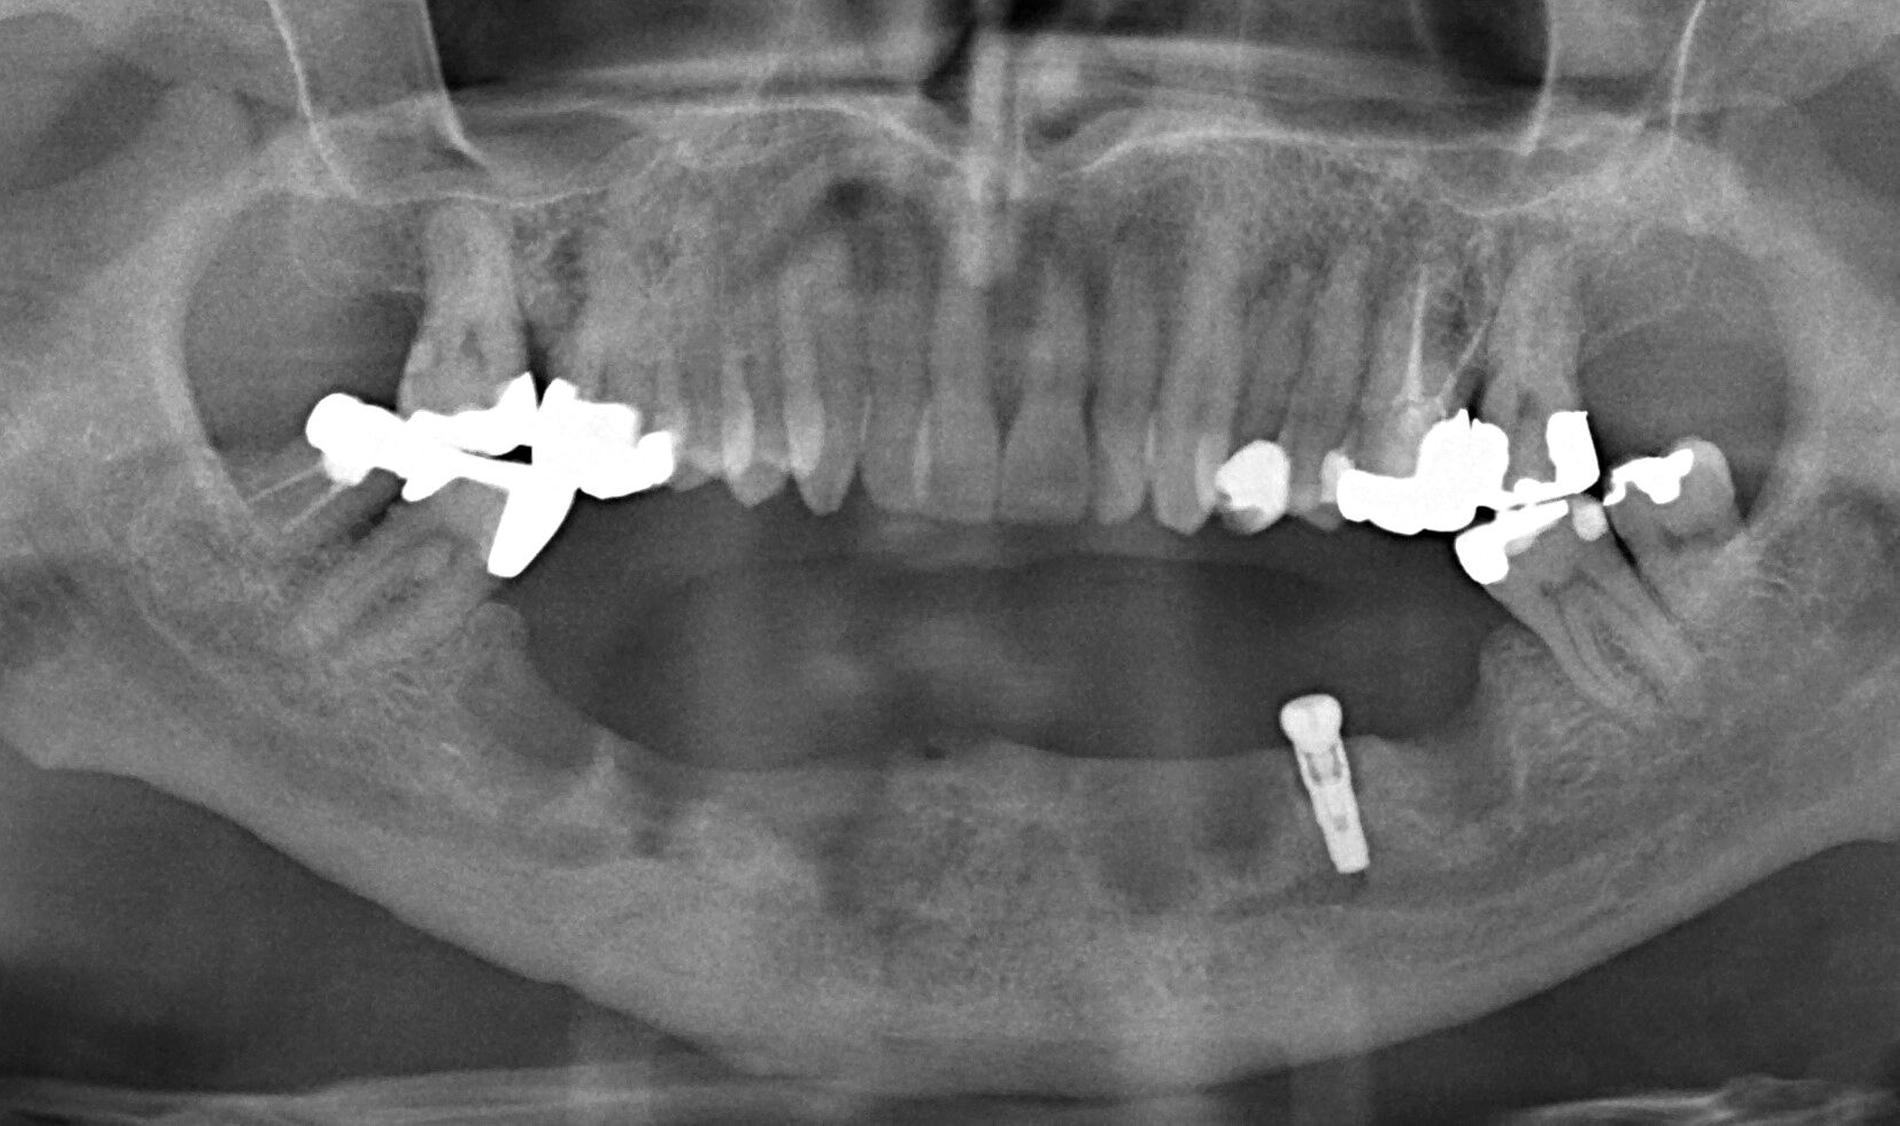

Nachdem der Patient bei einem Berufsunfall mit Ausnahme der zweiten Molaren und der Weisheitszähne alle Zähne im Unterkiefer verloren hatte, erfolgte 1996 im Alter von 44 Jahren die definitive Lückenversorgung. Hierzu wurden eine verschraubte Brückenkonstruktion (044-034-043-044) sowie zwei verblockte Kronenpaare auf insgesamt acht Implantaten eingesetzt. Nach sieben Jahren Tragedauer wurde an mehreren Implantaten röntgenologisch ein Knochenabbau festgestellt. Verkürzte Kontrollintervalle mit professionellen Zahnreinigungen und intensiven Instruktionen zur Interdentalhygiene konnten nicht verhindern, dass nach weiteren sieben Jahren Anfang 2011 der Knochenverlust an den meisten Implantaten auf 50 bis 80 Prozent zunahm (Abb. 1a).

Die Entscheidung zur Explantation fiel wegen des beschleunigten Knochenverlusts und der extrem erschwerten Bedingungen für eine effektive Mundhygiene im Bereich der Implantate mit Sondierungstiefen bis zu 12 mm (Abb. 1b und 1c). Unter Lokalanästhesie wurden sieben der acht Implantate mit einem passenden Trepanbohrer mit 0,1 mm Aufmaß im Vergleich zum Außendurchmesser der Implantate umbohrt, anschließend mit einem kleinen Rasparatorium gelockert und dann mit einer Arterienklemme entfernt. Entscheidend für die Eignung der Trepanbohrer war die Längenmarkierung, um eine Nervverletzung bei der Entfernung der sehr tief gesetzten Seitenzahnimplantate zu vermeiden (Abb. 1d und 1e). Eine ausgedehnte Lappenbildung konnte durch dieses Vorgehen vermieden werden.

Eine präoperativ vorbereitete Interimsprothese, die über zwei gegossene Bonwill-Klammern sowie das verbliebene Implantat in regio 35 stabil abgestützt war, diente gleichzeitig als Verbandsplatte (Abb. 1f). Auf eine Glättung scharfer Knochenkanten oder die Nivellierung der Kieferkämme wurde verzichtet, um einen iatrogenen Knochenverlust zu vermeiden und das regenerative Potenzial des verbliebenen Knochens zu nutzen (Abb. 1g). Bereits bei der röntgenologischen Kontrolle nach drei Monaten war eine deutliche Zunahme des Knochens im Bereich der alten Implantatpositionen zu erkennen (Abb. 1h). Eine Nachimplantation von vier Implantaten in den Positionen 32, 34, 42 und 44 erfolgte neun Monate nach der Explantation und einer vorangegangenen Verbesserung der Weichgewebsbedeckung durch multiple freie Schleimhautransplantate vom harten Gaumen. Die knöcherne Regeneration unter der gut abgestützten Modellgussprothese verlief so günstig, dass sich der vertikale Höhenverlust des Alveolarkamms im Bereich der gescheiterten Implantate auf circa 2 mm begrenzen ließ. Das zur Entlastung der Kieferkämme und der einheilenden Implantate außerordentlich hilfreiche Implantat in regio 35 wurde erst nach dem Einheilen der nachgesetzten Implantate entfernt. Nach der Einheilzeit der Implantate von weiteren drei Monaten wurde eine kombiniert Zahn/Implantat-gestützte Teleskopprothese mit intraoral verklebten Galvano-Sekundärkronen eingegliedert (Abb. 1k bis 1m). Inzwischen ist diese, wie eine herausnehmbare Brücke abgestützte UK-Prothese seit zehn Jahren funktionstüchtig ohne Zeichen einer Periimplantitis an den vier Implantaten.